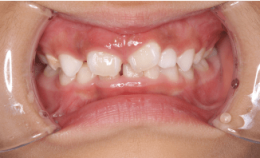

1.未就学児に行う矯正治療とは?

未就学児に行う矯正治療の主な目的

- 口呼吸の改善

- 舌癖の改善

口呼吸をしていると前歯が前に出てしまい出っ歯になったりします。また、舌で歯を押す癖があると、歯が前の方に倒れていって隙間のあいた歯並びになってしまいます。

写真①:使用する装置例

写真①の装置を就寝時に使用することでこれらを改善していきます。